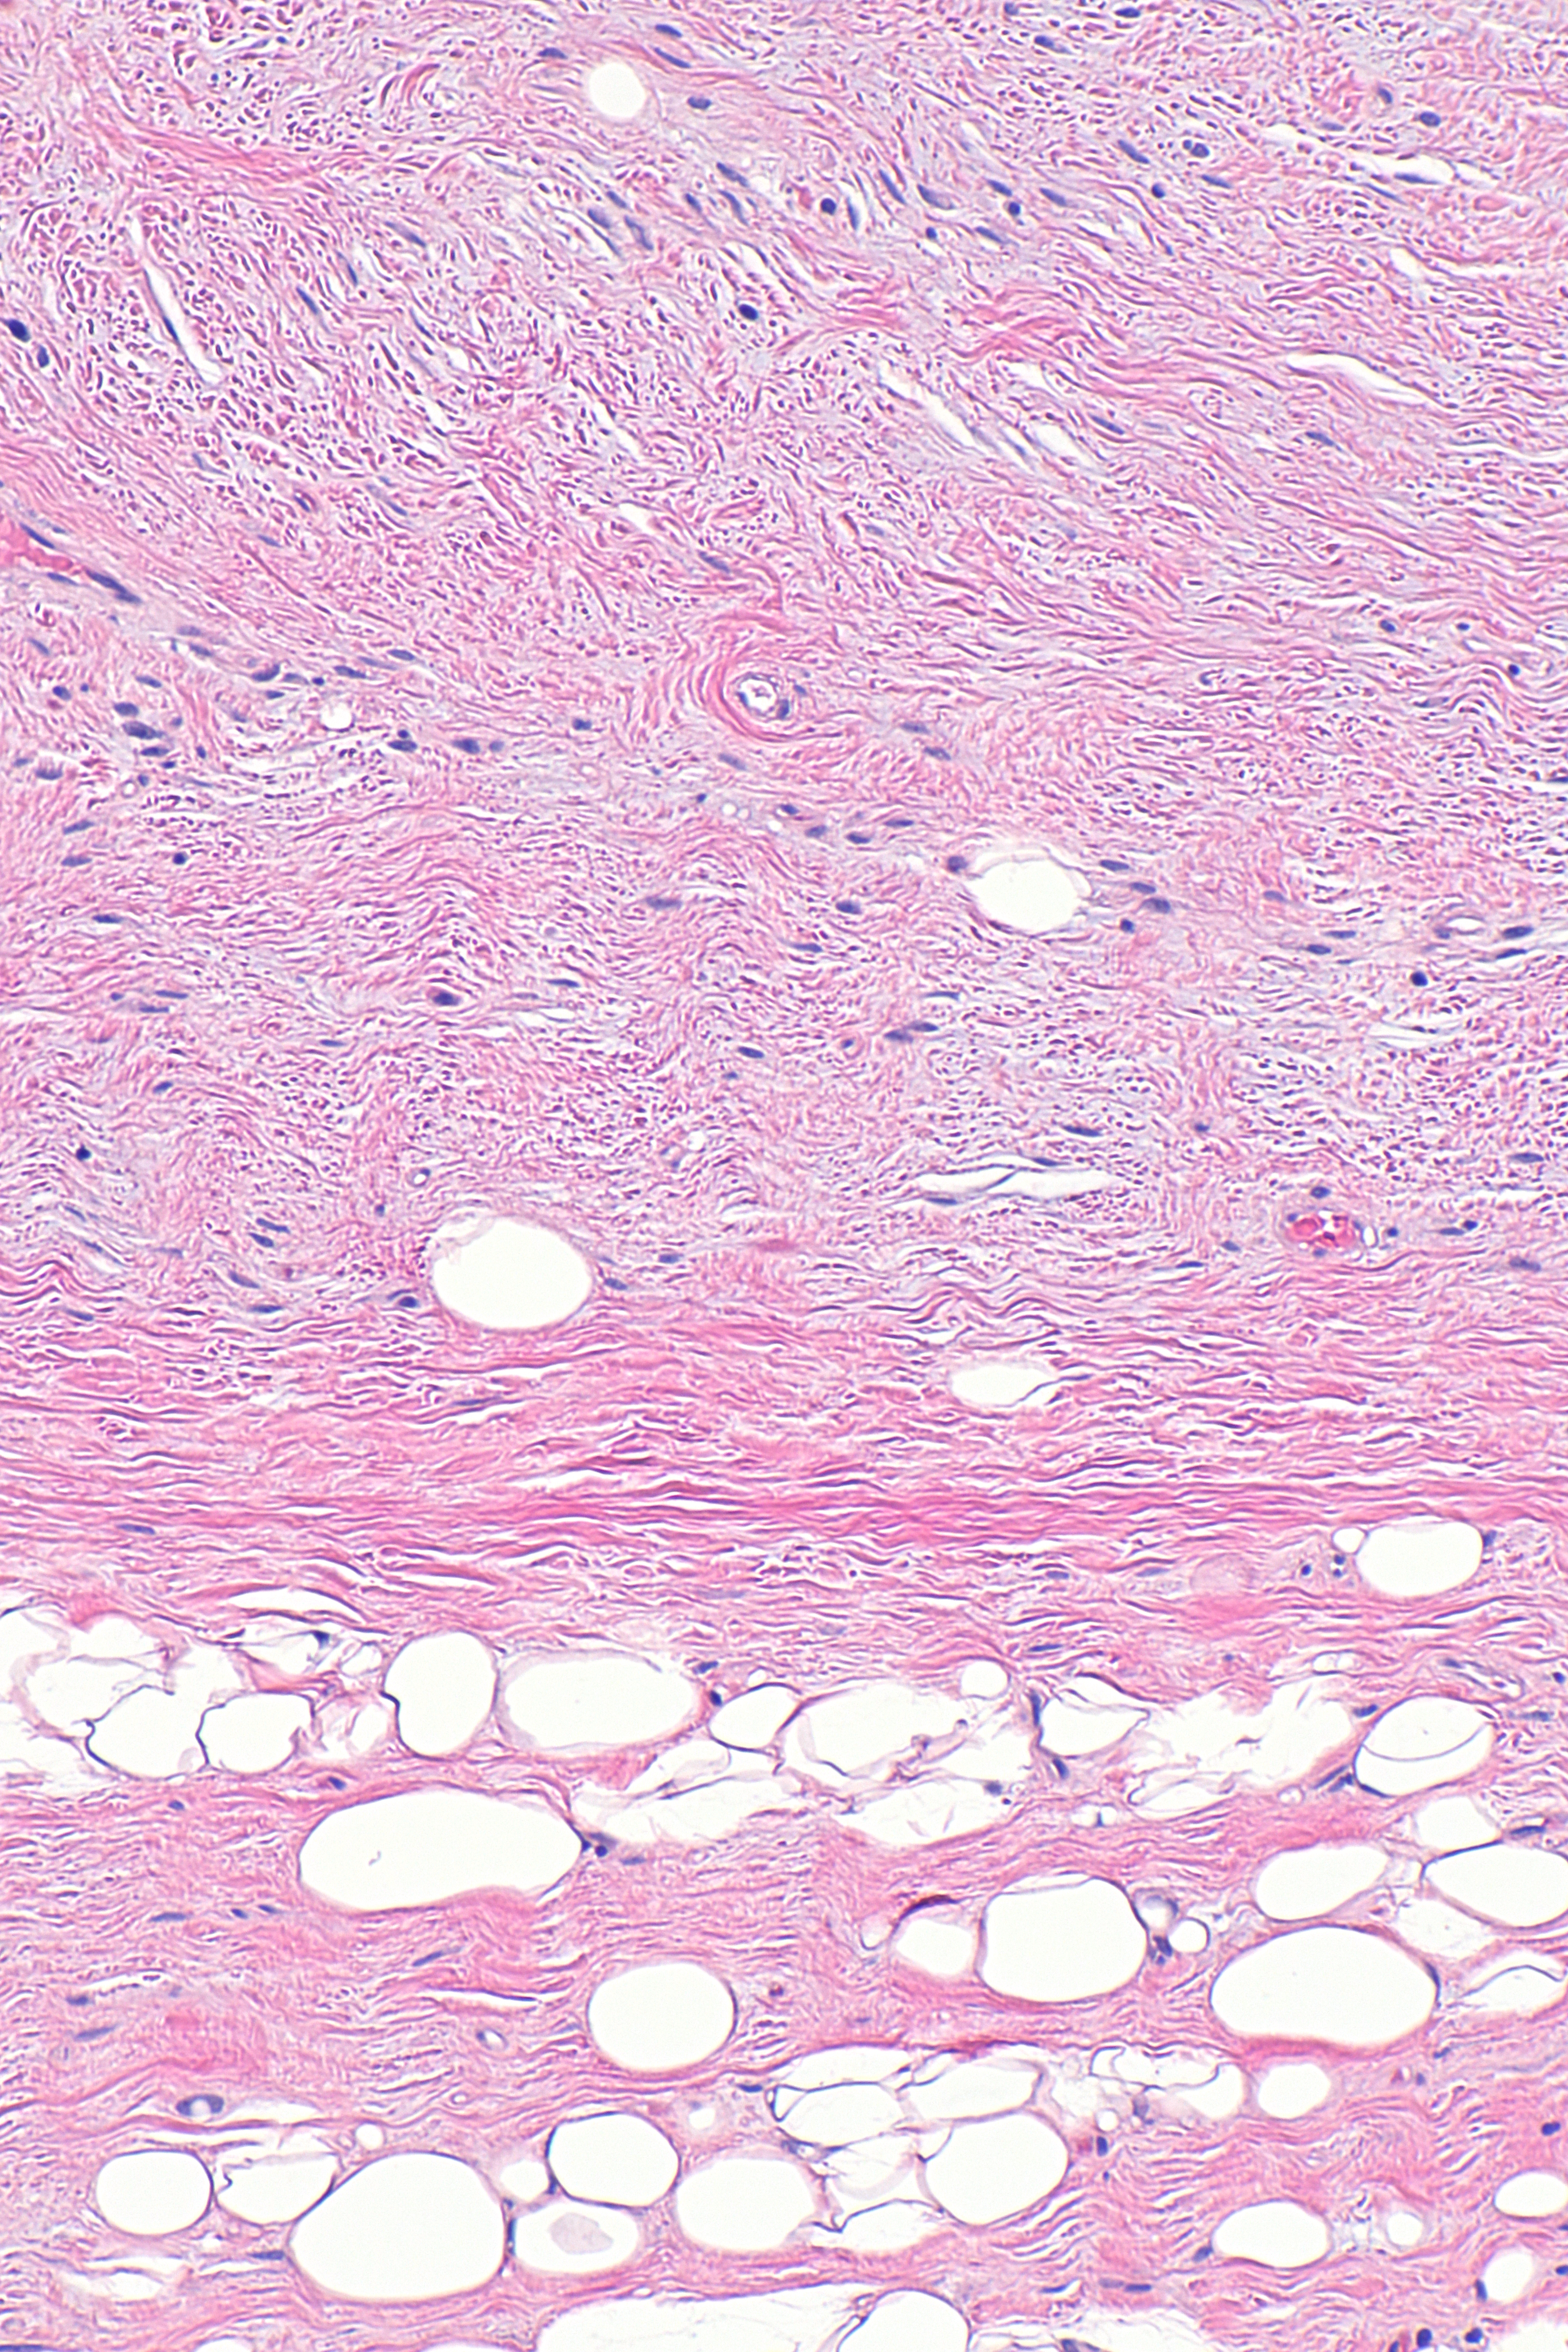

Микроскопические исследования липомы: гистология и патанатомия